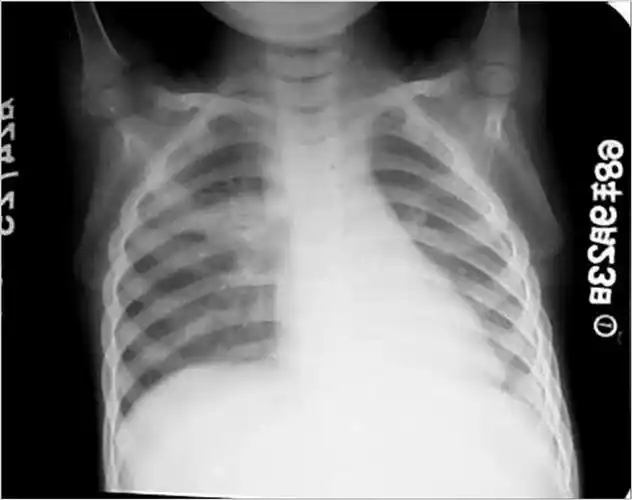

影像检查发现肺部有阴影,是肺癌吗?

肺结核的影像学诊断

淋巴管炎和肺门淋巴结结核称为原发综合征,x线呈哑铃状阴影,临床上

原发性综合症